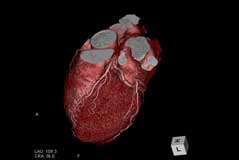

冠動脈CT検査

狭心症や心筋梗塞などの虚血性心疾患の原因は、心臓の筋肉に血液を供給する「冠動脈」の動脈硬化です。最新のマルチスライスCT(128スライス)を使用して「冠動脈」を評価する事で、突然死の一因である心筋梗塞などを未然に防ぎます。

「冠動脈」の評価は従来カテーテル検査で行われてきましたが、近年より冠動脈CT検査が多く行われるようになりました。八王子クリニックでは2003年から冠動脈CT検査に取り組み、長年にわたり撮影技術の向上に努めています。